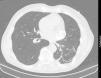

No ecocardiograma observa‐se uma imagem de massa arredondada com paredes calcificadas, assente sobre a aurícula esquerda (onde é ligeiramente compressiva) e o sulco auriculoventricular das paredes lateral e anterior, cuja fibrocalcificação parece envolver o miocárdio do segmento basal da parede lateral (mais fino, hiperecogénico e acinético) (Figura 2). A angio‐TC descreve a lesão dentro do saco pericárdico em posição alta e com amplo contacto com o pericárdio sugerindo epicentro nesta estrutura. A lesão aparenta ter uma origem extravascular podendo ser de origem sequelar a traumatismo antigo (Figura 3).